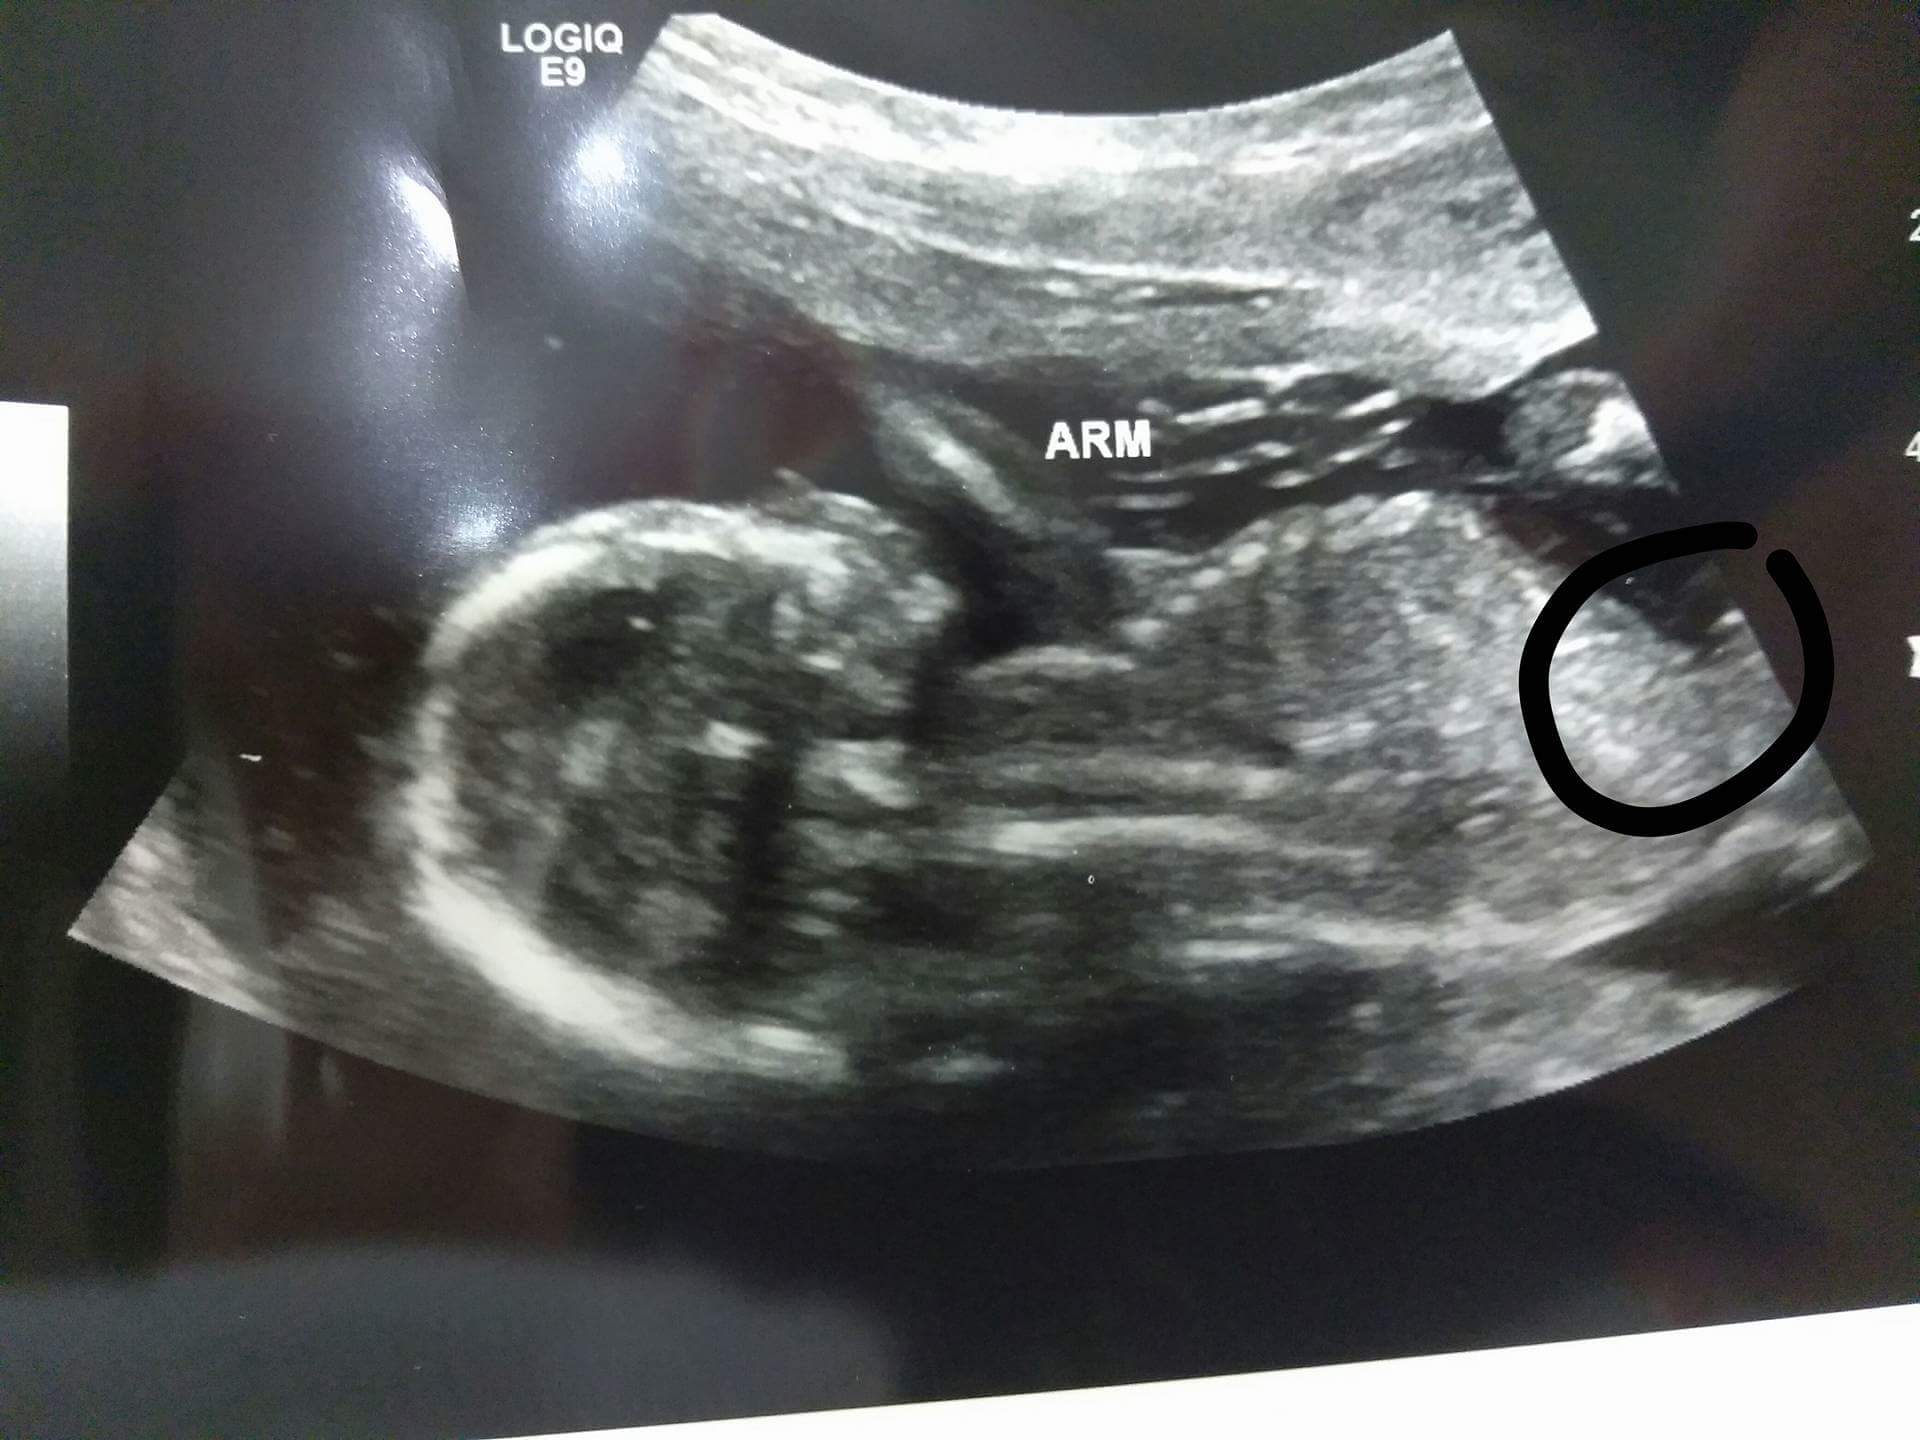

This is a closer picture I swear it looks like a vagina

Attachment 37541